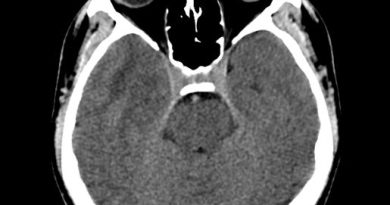

15 yaş kız çocuk

8 yıldır ara ara karın ağrısı, kusma, ishal/kabızlık

3-4 aydır düşük ayak

mitochondrial neurogastrointestinal encephalomyopathy (MNGIE)

Mitochondrial neurogastrointestinal encephalomyopathy syndrome